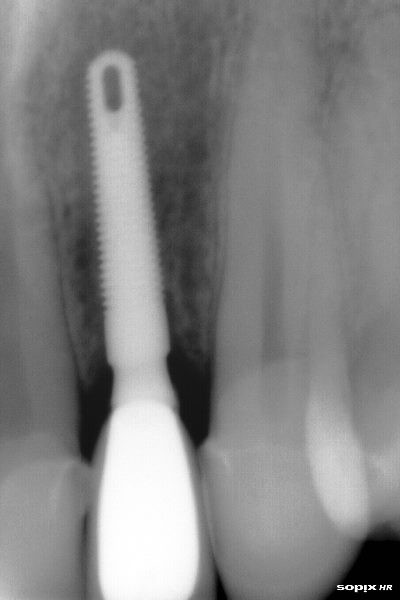

Radiografía inicial

Radiografía final